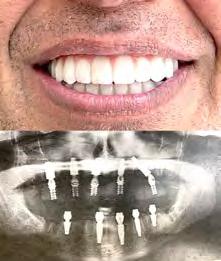

# 7 (2024) • 7 апреля Газета «Диаспора» – все о нас с вами ПО ВОПРОСАМ РАЗМЕЩЕНИЯ РЕКЛАМЫ ОБРАЩАЙТЕСЬ ПО ТЕЛЕФОНУ: (916) 487-9701 или (916) 705-0739 10 Замещение всех зубов на 4-х, 6-ти имплантах Одиночные импланты Несколько имплантов ИМПЛАНТАЦИЯ ЗУБОВ Установка одного импланта от FREE Consultation and CT-Scan Лучшее качество услуг и материалов по разумной цене! Консультация и 3D снимок в подарок. 911 Reserve Dr., Ste #150, Roseville, CA 95678 | Phone: (916) 827-3605 $998* (916) 827-3605 Высококлассные услуги по Зубной Имплантации в современной клинике, лимиторованной на установку имплантов. * - установка 1 (одного) импланта не включая абатмент и коронку. Имплантация будет производится одним из специалистов клиники под руководством доктора Александра Антипова, челюстно-лицевого хирурга. Цена указана для пациентов, оплачивающих наличными.

день Одна из недавних операций:

Все-на-5-ти имплантах +

зубы за 1